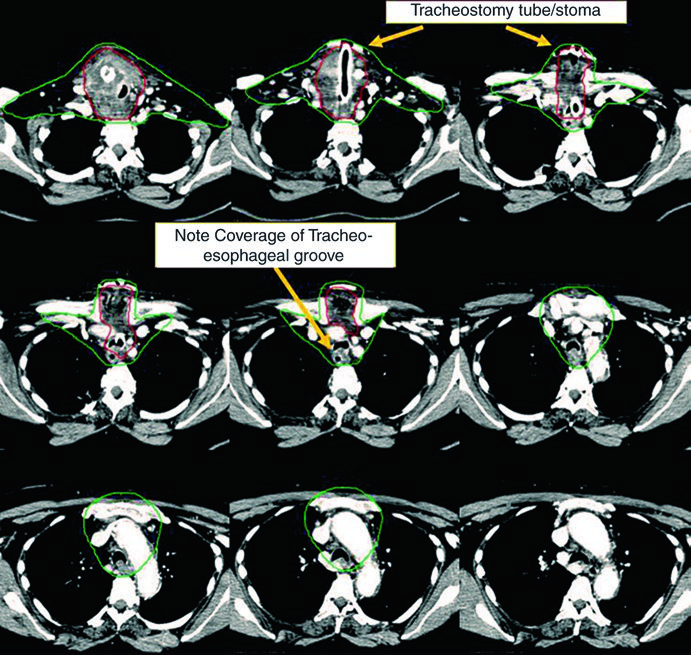

Caso 1 — Carcinoma papilar metastático (Fig. 9.1): Homem de 58 anos com carcinoma papilar metastático de tireoide, submetido a múltiplas ressecções prévias, que se apresentou com recorrência local irressecável e múltiplos linfonodos mediastinais. Recebeu quimiorradioterapia definitiva para prevenir progressão local. O CTV70 Gy (vermelho) abrange a recorrência local e linfonodos mediastinais envolvidos, enquanto o CTV60 Gy (verde) cobre as regiões subclínicas de risco. Este caso exemplifica o cenário de doença recorrente que esgotou as opções cirúrgicas — a radioterapia com dose definitiva é a melhor alternativa para controle local.

Caso 2 — Carcinoma anaplásico irressecável (Fig. 9.2): Mulher de 73 anos com carcinoma anaplásico de tireoide invadindo laringe, traqueia e esôfago. Recebeu quimiorradioterapia definitiva com doxorrubicina concomitante. O CTV70 Gy (vermelho) engloba toda a doença volumosa, e o CTV60 Gy (verde) abrange o risco subclínico. Detalhe importante: o manúbrio, que normalmente não é incluído no volume de risco, foi englobado neste caso específico por conta da doença volumosa anterior agressiva no pescoço. Essa decisão é atípica e deve ser individualizada — não se trata de protocolo, mas de resposta a uma apresentação clínica particular.

Esses dois casos ilustram a versatilidade da IMRT com dose-painting: o plano entrega simultaneamente 70 Gy ao volume de alto risco e 60 Gy ao volume subclínico, sem necessidade de boost sequencial. A escolha de doxorrubicina como quimioterápico concomitante no anaplásico reflete a agressividade dessa histologia e a necessidade de sensibilização ao tratamento, embora as opções sistêmicas tenham evoluído significativamente nos últimos anos.